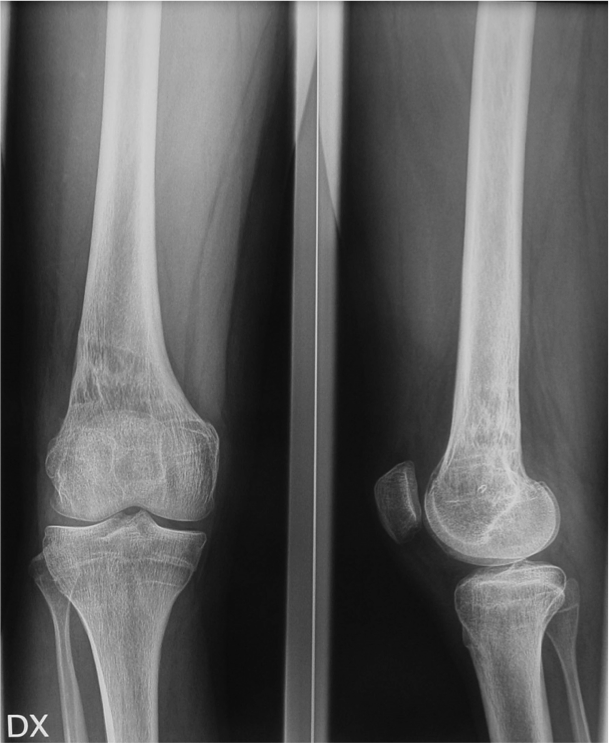

Risultato radiografico

Folow up clinico e radiografico a 3 anni